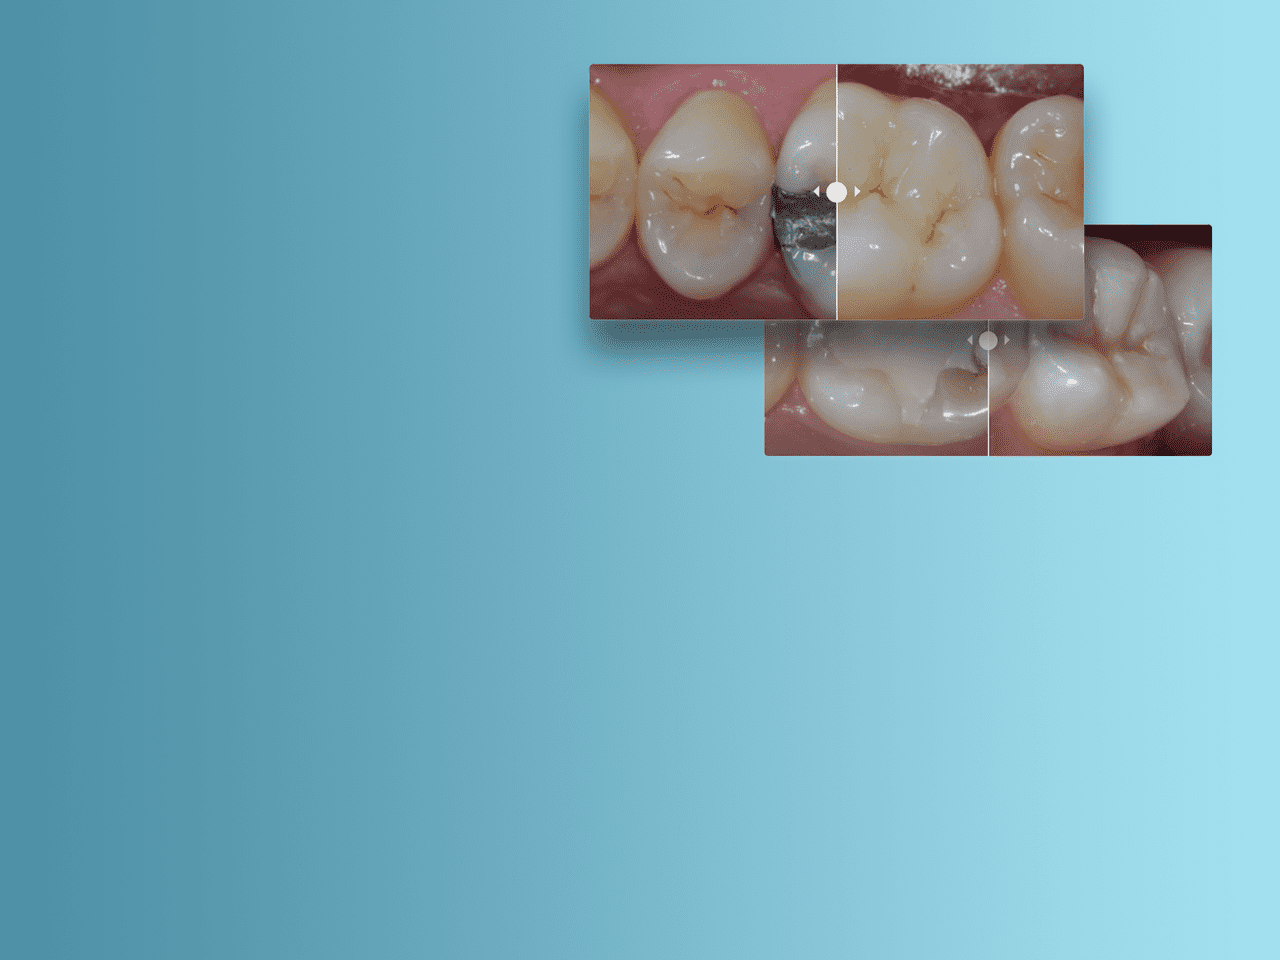

Imagen:

Antes: restauración posterior con composite restaurador Spectra ST de color A2 (Fuente: Dr. A. Ferrando)

Después: sustitución de amalgama con una técnica de estratificación avanzada, utilizando el color A2 y Bleach White del composite restaurador Spectra ST